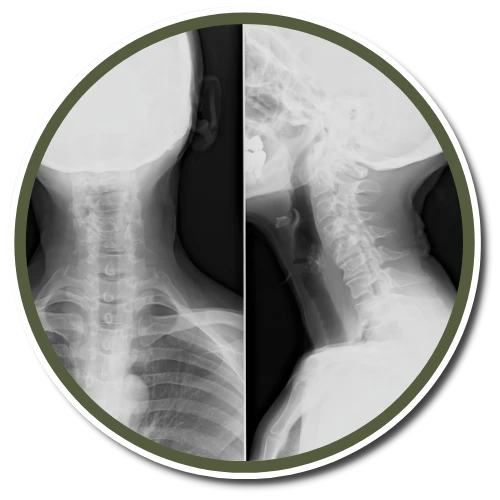

Sage Clinic uses the Gonstead method of adjusting and analyzing the spine. We're one of a few offices in Newtown Square that exclusively uses the Gonstead method. By thoroughly analyzing the spine through the use of x-ray, instrumentation, visualization, static and motion palpation you can expect a properly delivered adjustment.